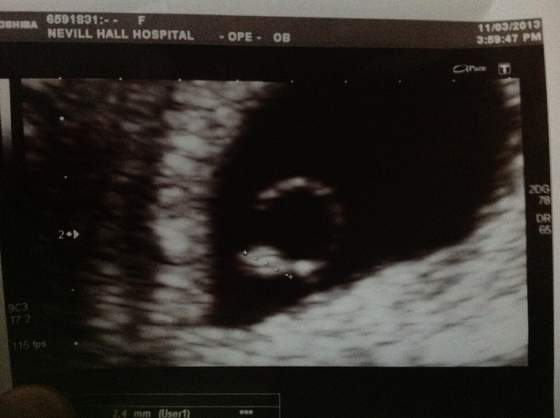

Dziewczyny jestem w ciezkim szoku! Moje malenstwo jest super przyczepione ma 2,4 mm i serduszko pieknie bije! Wszystko jest w jak najlepszym porzadku. Jedyne co to wielka systa na prawym jajniku ktora boli i nadzieja ze sie wchlonie. Ale ulga :)

ps. Widac ze skorpionek nie? Hihi

• image.jpg

image.jpg

16,1 KB · Wyświetleń: 59